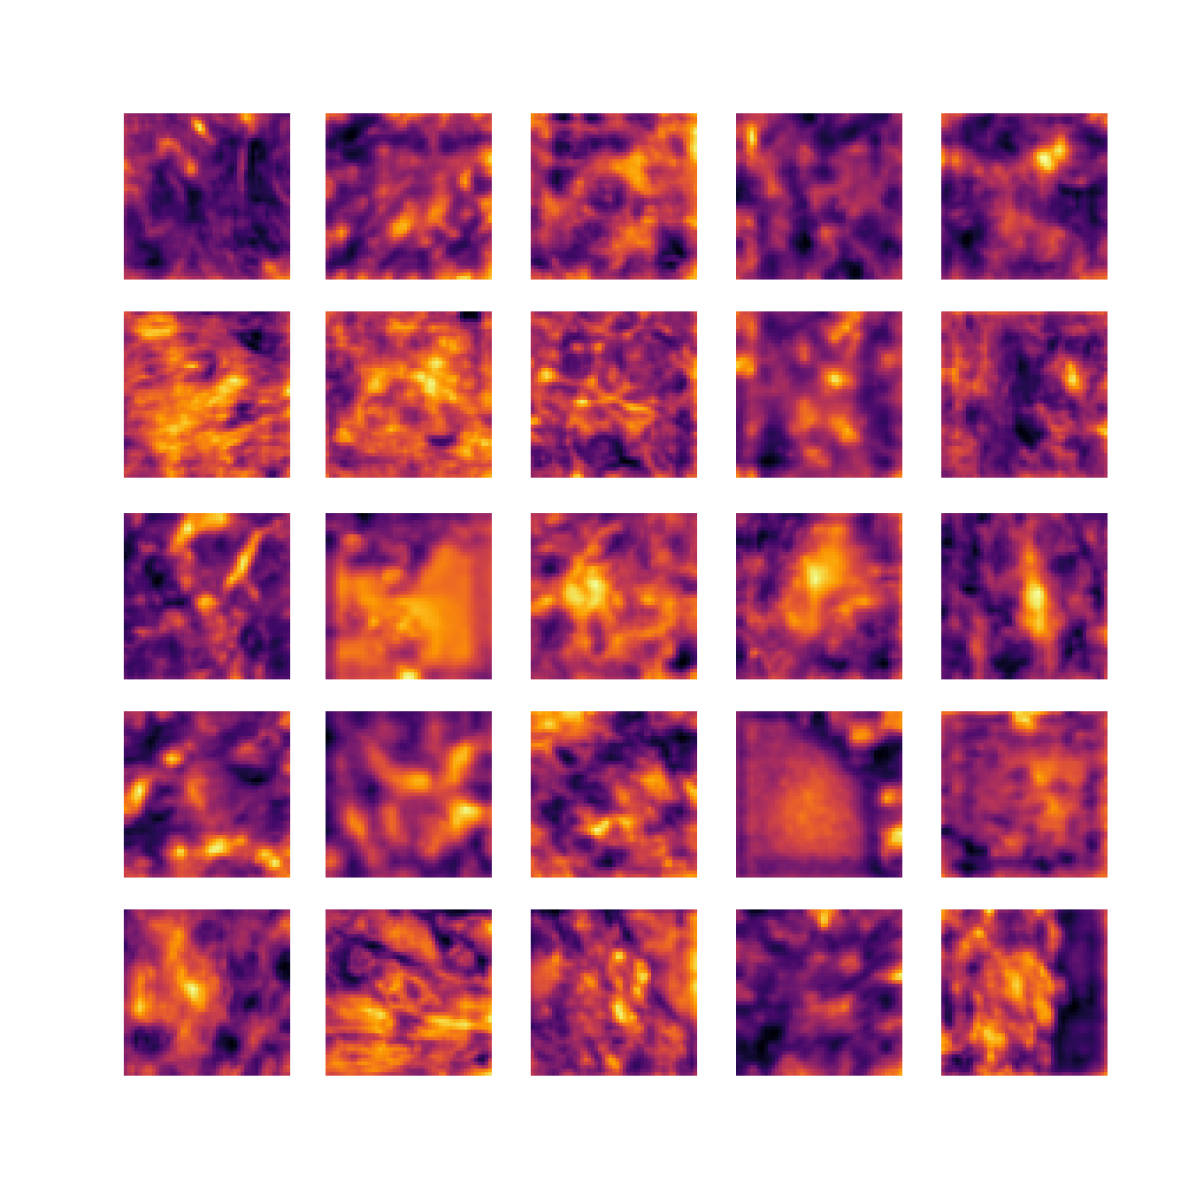

We also analyse the activation maps for each model using GradCAM as described in section S3. This offers more insight into the areas of the image which are contributing most heavily to the models’ representations. In Figure 4(b) we present some representative examples, however, a larger selection which was chosen at random is presented in Figures S10 to S25. The larger selection makes it easier to see the emergent patterns, including that privileged Siamese models tend to mainly identify features which are strongly present in both inputs, while unprivileged Siamese models tend to learn more diffuse features that are not specific to one cell phenotype or image region. TriDeNT ♆ incorporates both sets of features, learning both features specific to the privileged data and more the general features associated with unprivileged Siamese networks.

We can see in Figure 4(b) panel A that for ERG, the privileged Siamese model focuses almost exclusively on any nuclei which could be endothelial cells. As there are very few endothelial cells in the dataset, it could be an effective strategy to identify anything that could potentially be an endothelial cell to minimise the difference between the representations of the H&E model and the IF mask model. In the corresponding unprivileged Siamese image, we see that the model identifies some of these nuclei, albeit less strongly, but also focuses heavily on the other tissue and even the background, while strongly fixating on two spots of debris in the center of the image. This model has less ‘incentive’ to learn the weak features related to endothelial cells as these occur rarely and are not easy to detect, while more generic strong features such as the presence of connective tissue and the prevalence of background are more common and predictable from augmented images. We see that TriDeNT ♆ combines these two feature sets, strongly identifying nuclei while also identifying the connective tissue.

In panel C we see a similar pattern, with the privileged Siamese model fixating solely on the nuclei, while the TriDeNT ♆ model takes a more balanced approach. The unprivileged Siamese model appears to focus on a single cluster of nuclei while neglecting others, and similarly identifies an area of fibroblasts with its distinctive pattern but does not others.

In contrast to panels A and C which represent models with poor privileged Siamese results, panels B and D represent models whose privileged Siamese results were comparable to both TriDeNT ♆ and even the supervised baseline. It is therefore interesting to note that there are far more similarities between the privileged Siamese and TriDeNT ♆ models in both cases. Particularly in panel B, TriDeNT ♆ and the privileged Siamese model return virtually identical heatmaps, with both strongly identifying epithelial nuclei and neglecting the same areas of connective tissue. The unprivileged model in this case appears to focus solely on the centre of the image, giving a significantly different heatmap to the other panels.

Panel D again shows the previous pattern, with the privileged Siamese model identifying the features strongly present in the privileged data – fibroblasts – while neglecting the nuclei present. TriDeNT ♆ also strongly identifies the connective tissue, but, unlike the privileged Siamese model, does not completely neglect the nuclei. The unprivileged Siamese model primarily identifies background, and does not appear to identify the nuclei in this example.